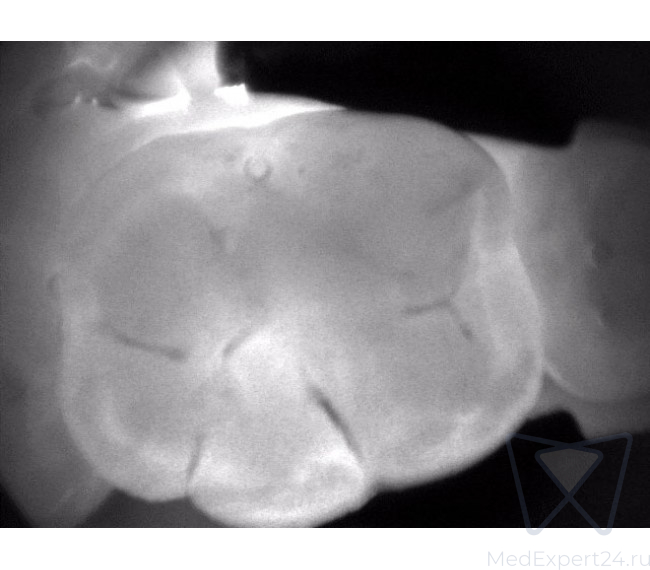

KaVo DIAGNOcam дает Вам полную уверенность в точности результата диагностики. С его помощью Вы сможете обнаружить кариозные поражения на самом раннем этапе развития.

KaVo DIAGNOcam позволяет визуализировать их на аппроксимальных и окклюзионных поверхностях зубов и обеспечивает проведение диагностики вторичного кариеса (при небольшом размере пломбы).